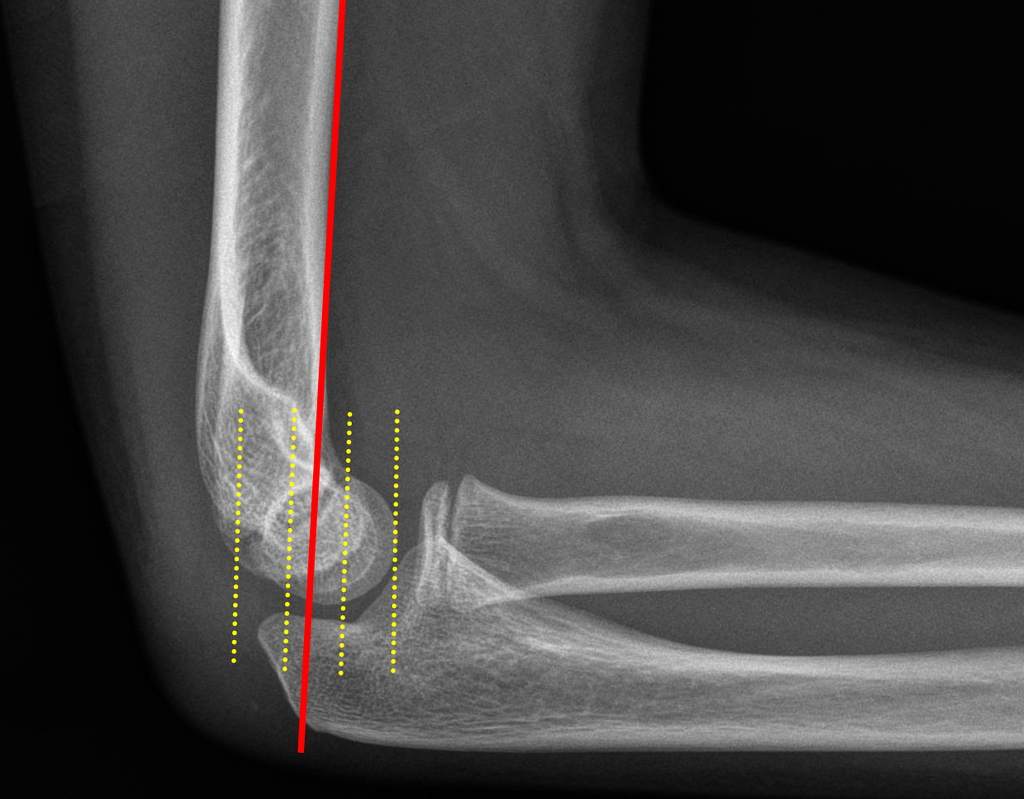

humeral line anterior elbow supracondylar pediatric fractures normal radiology fracture humerus radiopaedia capitellum angle capitulum joint case types injuries occult

elbow ray radial fracture head normal alignment line anterior humeral coreem

elbow forearm normal lateral alignment anterior capitellum radiograph interpreting radiographs fracture supracondylar intersect

elbow line anterior normal radiocapitellar humeral fractures adults lateral radiograph dislocations imaging

humeral radiocapitellar elbow radiographic

elbow humeral fracture supracondylar forearm capitellum radiographs interpreting intersect

elbow xrays humeral radiocapitellar emdocs fracture

elbow xrays anterior humeral radiocapitellar emdocs fracture

humeral lateral elbow rogers

radiopaedia line humeral anterior radiology

capitellum dislocation elbow pediatric through drawn lateral anterior humeral pass should line

Anterior humeral line. Pediatric humeral fracture. Elbow injuries